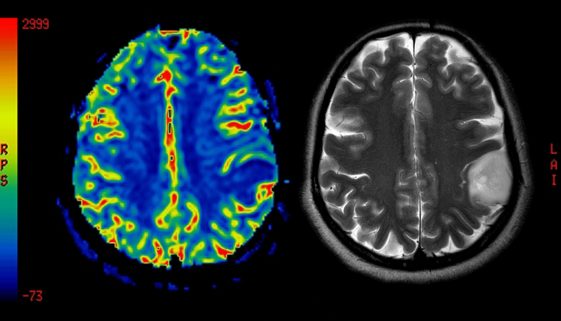

تعد جراحة أورام المخ من الإجراءات الطبية المعقدة التي تتطلب فهمًا دقيقًا للمرض وكيفية التعامل معه. إليك نصائح وتعليمات تثقيفية تساعد المرضى وعائلاتهم على استيعاب هذا الموضوع بشكل أفضل. تعتبر أورام المخ من الحالات الطبية الصعبة نظرًا لاستقرارها في مركز الجهاز العصبي الذي يتحكم في العديد من الوظائف الحيوية. تتطلب […]